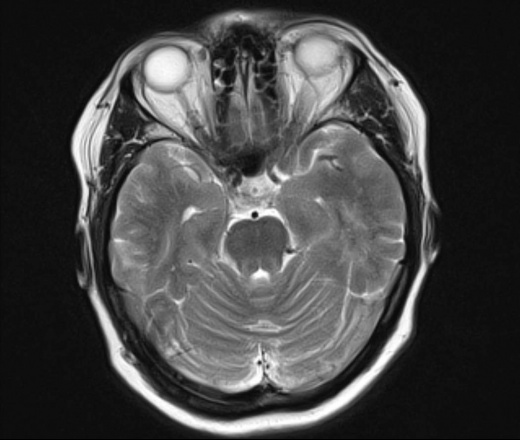

У пациентки 1960 г.р. с 2005 наблюдается птоз, диагноз миастении исключен. МРТ ГМ впервые выполнено в августе 2015 г в плановом порядке, новых жалоб не было, по описанию МРТ - очаговые изменения белого и серого вещества больших полушарий и ствола мозга - признаки энцефаломиелита.

В сентябре 2015 новое МРТ: субкортикальные очаги в белом веществе больших полушарий, не накапливающие контраст; уменьшение размеров ряда очагов - Данных за демиелинизирующее заболевание нет, поствоспалительные изменения. Консультирована в НИИ неврологии, предположено демиелинизирующее заболевание вторичного генеза. В неврологическом статусе: правосторонний птоз, ограничение конвергенции, асимметрия носогубных складок.

Сейчас вновь сделано МРТ, появлись 2 новых очага: в полюсе правой височной доли и поперечной височной извилине слева. Очаг в задних отделах левой теменной доли (угловая извилина) увеличился в размерах. С контрастом пока не работаем.

Подскажите, пожалуйста, что это за процесс? Поражено только белое вещество или серое также? Есть ли поражение ствола мозга?

Действительно, динамика отрицательная и на первичную демиелинизацию не тянет. Какой-то продолжающийся энцефалит, какой именно и гадать нечего, это не наше дело, навскидку можно написать длинный ряд типа Эбштейна-Барра и пр, всё требует серологического доказательства.. В стволе ничего не увидел. Поражено белое и серое вещество.